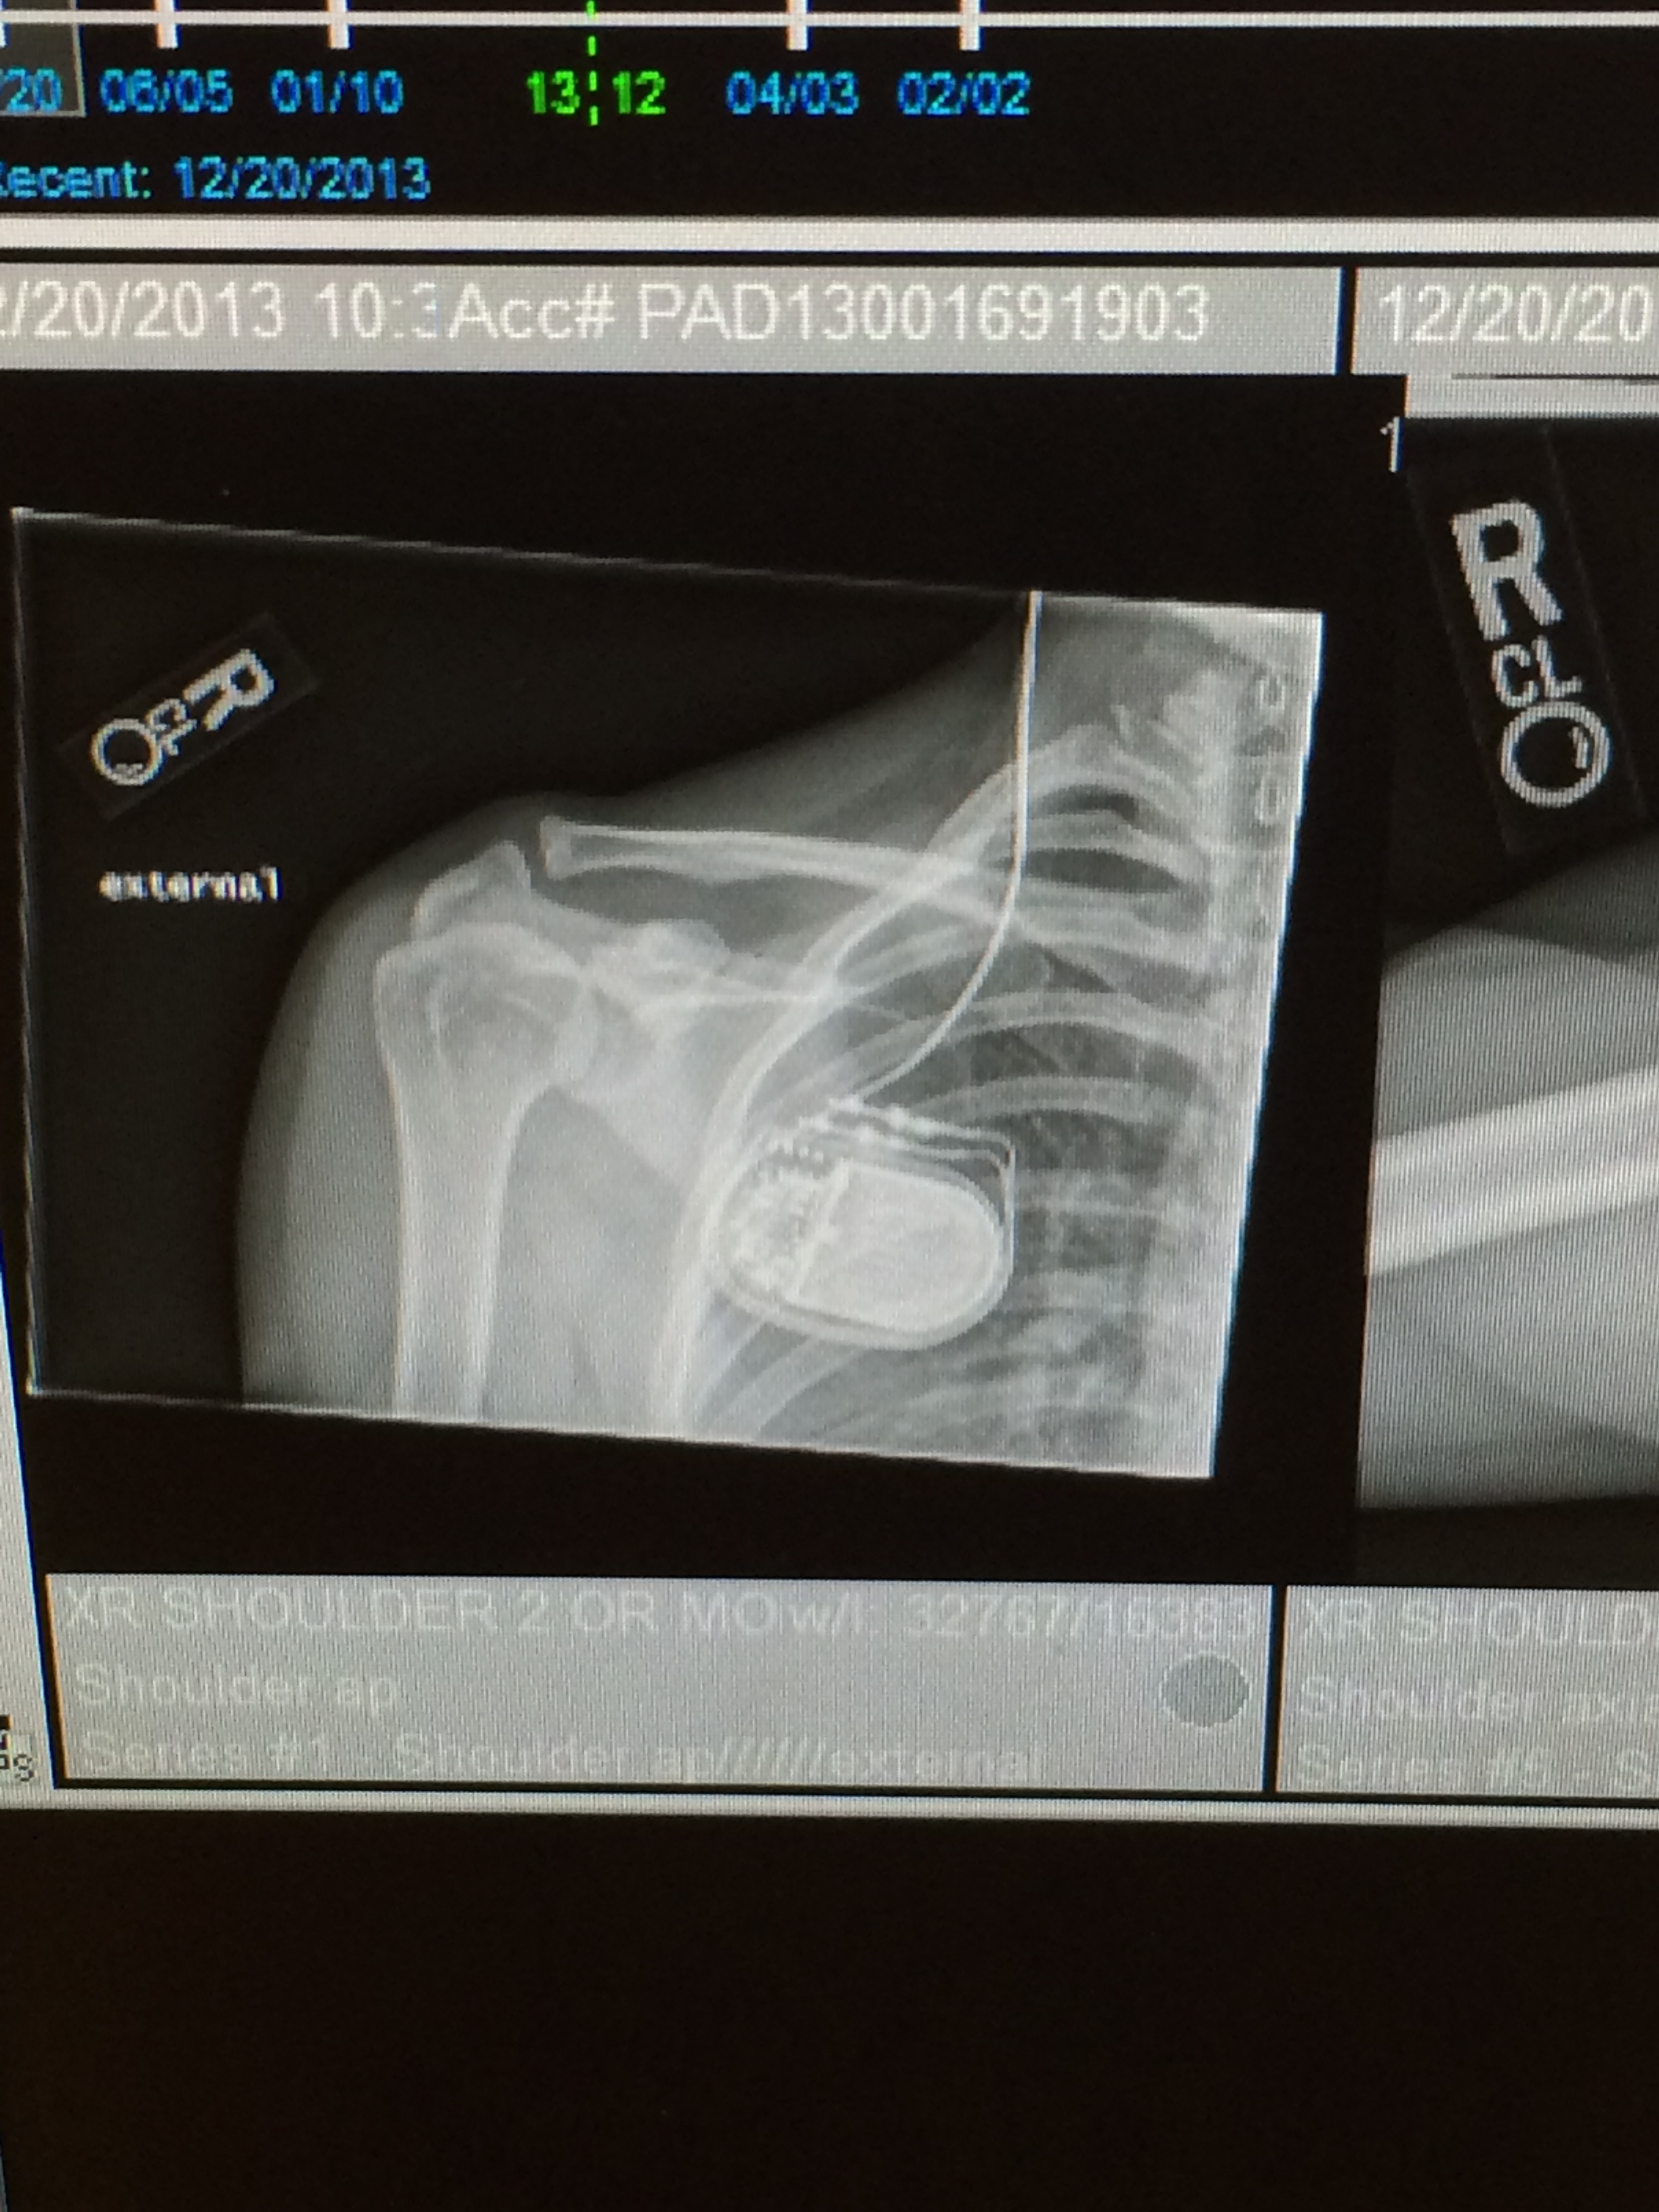

My friends came out – Mile 11, Mile 19, Mile 22 and Mile 23. Those hugs got me through all the miles. I never once thought I wouldn’t finish, even when I cramped up on the queensboro bridge with the sharpest pains in my inner thighs. I knew I was stronger than these temporary pains. Every hug energized me, every smile reminded me of every surgery and every battery malfunction I have ever had….then came the moment that I will never forget..

Probably one of the most surreal moments of my life – I ran by the same door I came out of 12 years ago – April 4, 2006 right after my brain surgery after I left the ICU…I saw myself being wheeled out on the chilly morning and here I was jogging every so slowly in front of the same door….I stopped. I cried, I lost my breath. I realized what I felt was lost in my life – my purpose. I had forgot what a life I had, what a miracle God had gifted me and I felt like I received that miracle again! The last 3 miles were hard, I was tired, my left foot hurt, I wanted to be done…so I did what so many people told me to do – keep moving forward, don’t stop just one foot in front of the other….then it happened…